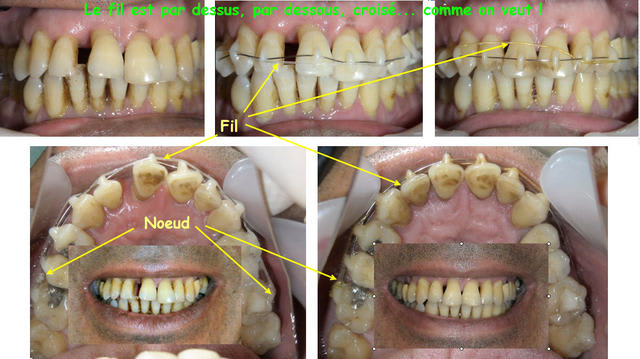

C'était ce matin, j'en ai profité pour faire ces photos à votre intention.

Des questions sur la procédure ?

Daniel

S'il y a un NiTi, c'est au dessus des ponts de composite. Il suffit de faire un noeud de chaque coté et le passer par dessus le fil, par dessous.., comme on veut. Il faut simplement qu'il ne puisse pas glisser jusqu'à la gencive.